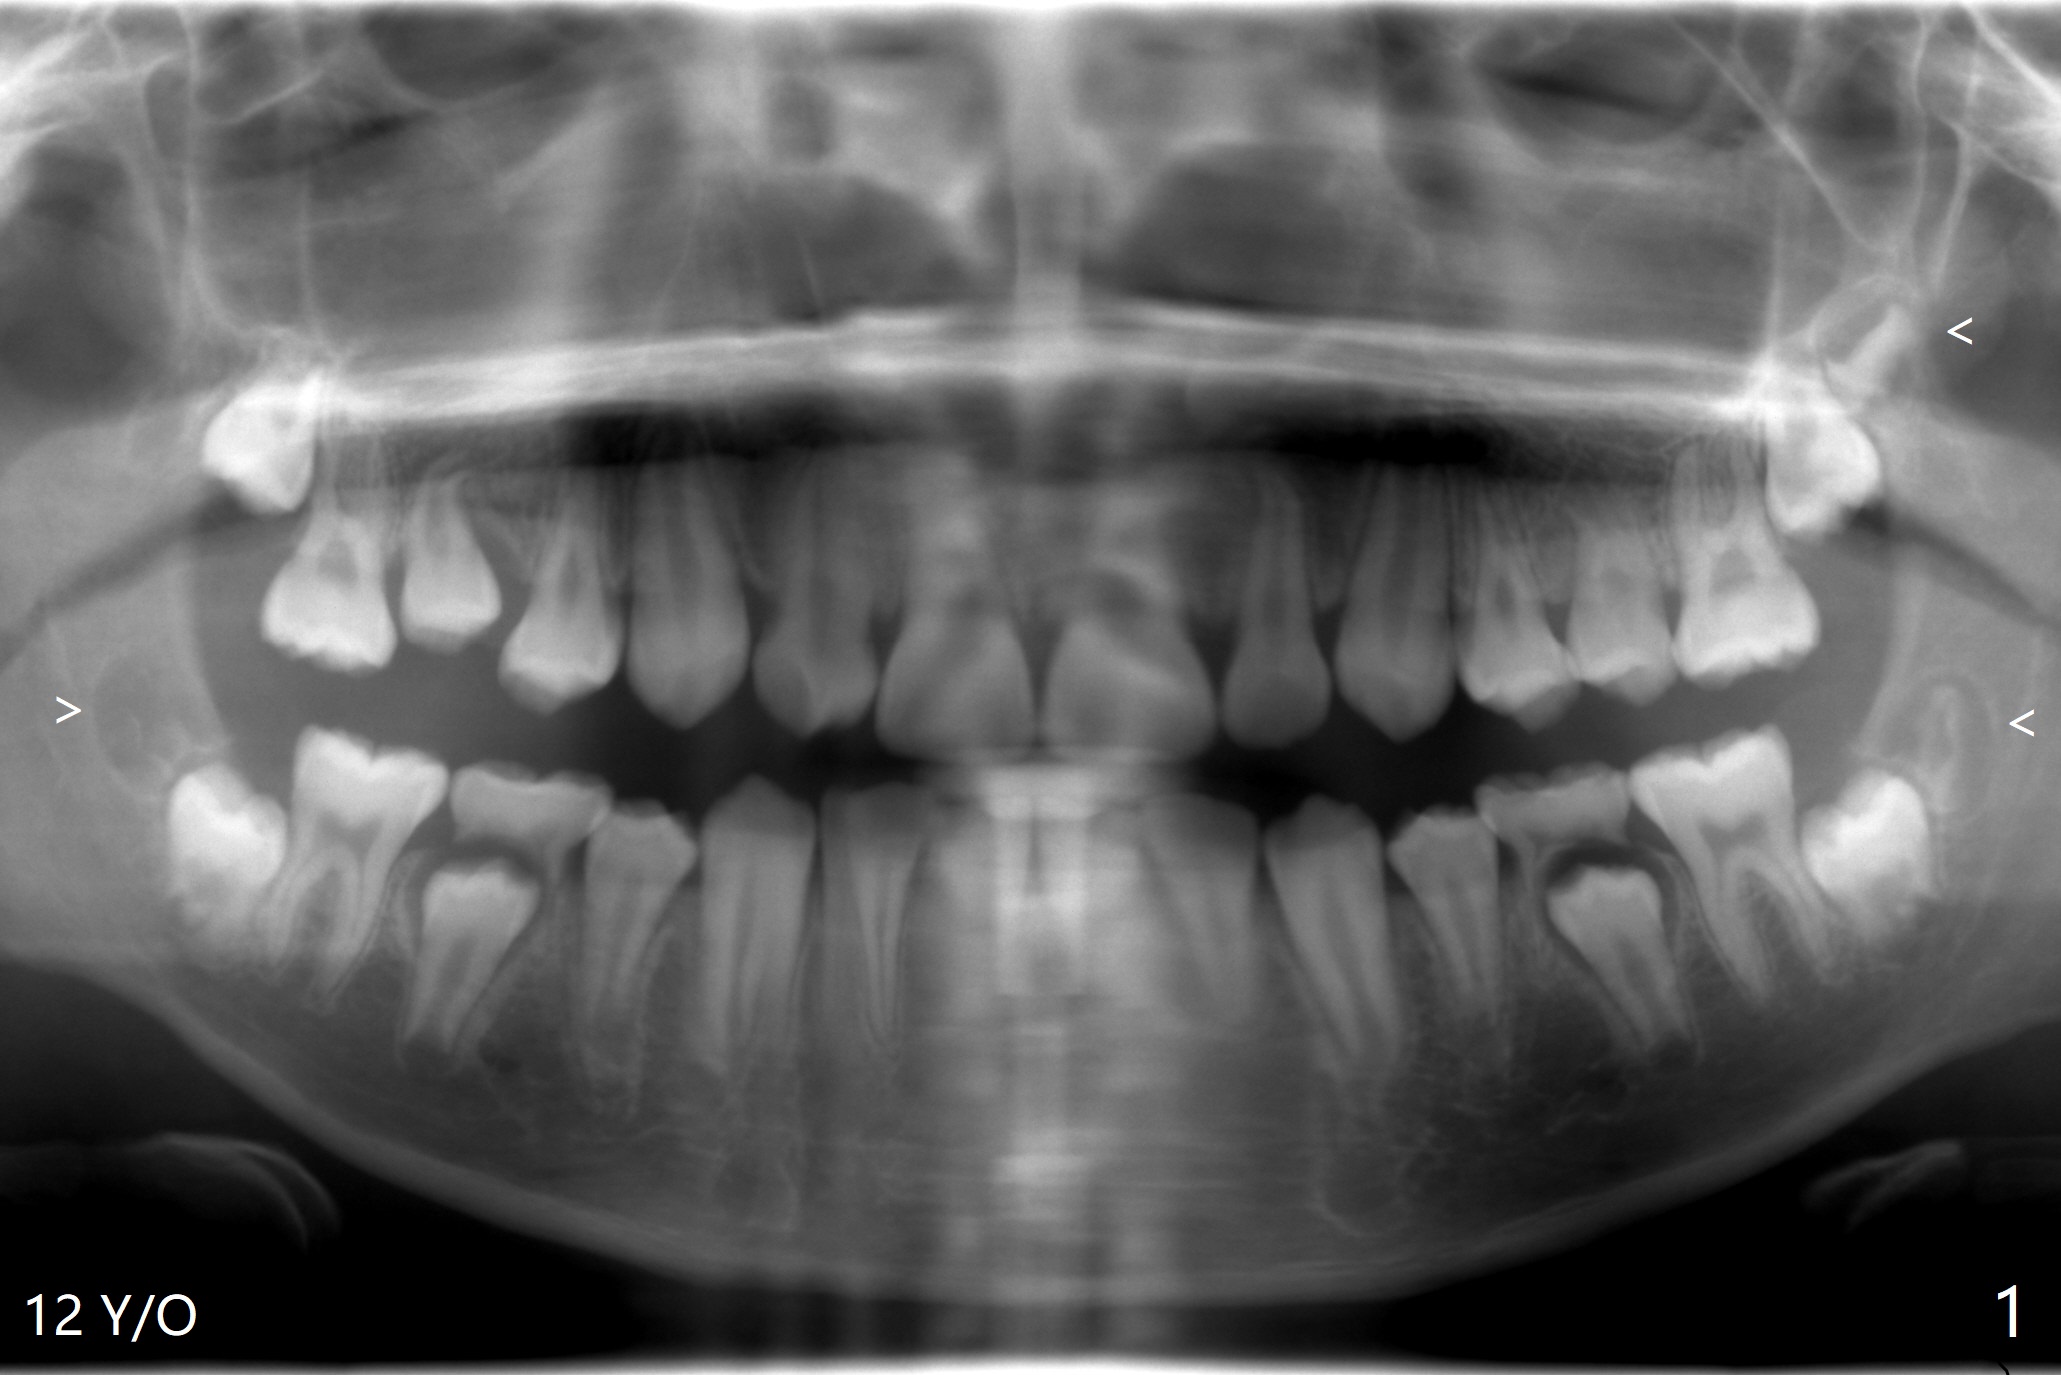

A 22-year-old man will return for 3rd molar extraction (4 of them, Fig.1-4). Prepare 2 or 3 #15 blades and 1-2 extra surgical burs. Since the third molars may overlap with the second ones, oblique incision (red line in Fig.4') will be mesial. Place Collagen and Osteogen plugs in the #32 and 17 sockets, respectively (Fig.4': C, O). As the roots are short and bone formation distal to the 2nd molars is critical, the plugs will be placed horizontally and coronally (Fig.4' white outline). No dovetail is needed. Pan 4 BW will be taken immediately and 3-4 months postop. The experiment will confirm whether collagen plug is enough to facilitate socket bone healing. In fact extraction of #1 turns out to be extremely difficult. There is not enough time for #16 and 17 extraction in one appointment (Fig.5).